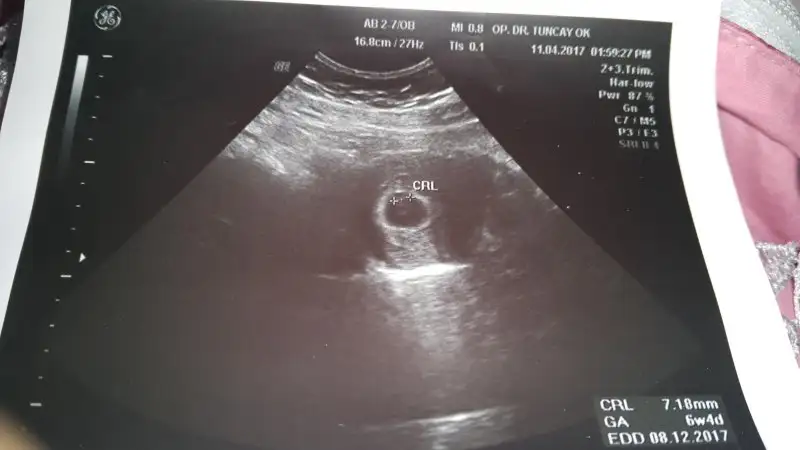

Ramzi teorisine göre ( bilimsel bir araştırma sonucuymuş ve %85 doğruluğu varmış). İlk 6-8 haftalık ultrason görüntüsüne göre bebeğin kesenin içersinde soldan ya da sağdan girişine göre cinsiyet tahmini yapılıyor. Bilimsel olunca tecrübeli annelerimiz yada anne adaylarımızdan yardım istiyoruz. Doğruluğu var mı öğrenmek adına :) Bizleri aydınlatırsanız çok seviniriz. bu teorieye göre;

Vajinal muayeneyle bakıldıysa eğer;

Sağdan girmiş gözüküyosa aslında solmuş ve ERKEK,

Soldan girmiş gözüküyosa aslında sağmış ve KIZ ,

Karından bakıldıysa eğer,

Soldan girmiş gözüküyosa gerçektede solmuş ve ERKEK,

Sağdan girmiş gözüküyosa gerçekte de sağmış ve KIZ,

Acaba Ramzi teorisi ve genital nub çıkıntısına göre söyleyebilir misiniz hanımlar